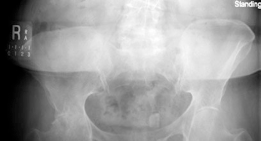

Clinical & Radiographic Imaging